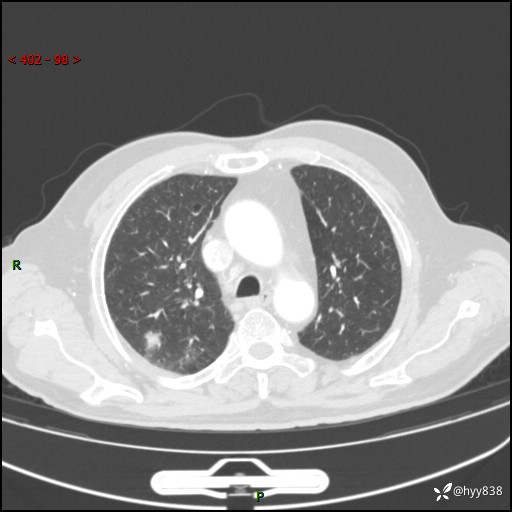

现病史:患者4月前无明显诱因后背正中间疼痛,间断阵痛,无低热、咳嗽,盗汗、咯血、胸痛、喘气等不适,2024-2-25当地市第二人民医院胸部CT提示“1.双肺感染病变;2.右肺中叶结节灶;3.双肺肺气肿并肺大泡4.主动脉及冠脉硬化,今为求明显结节性质遂来我院门诊就诊,门诊以“肺占位”收治入院。 起病以来,患者精神饮食睡眠一般,大小便正常,体力体重无明细变化。

胸部CT平扫(2024.2)